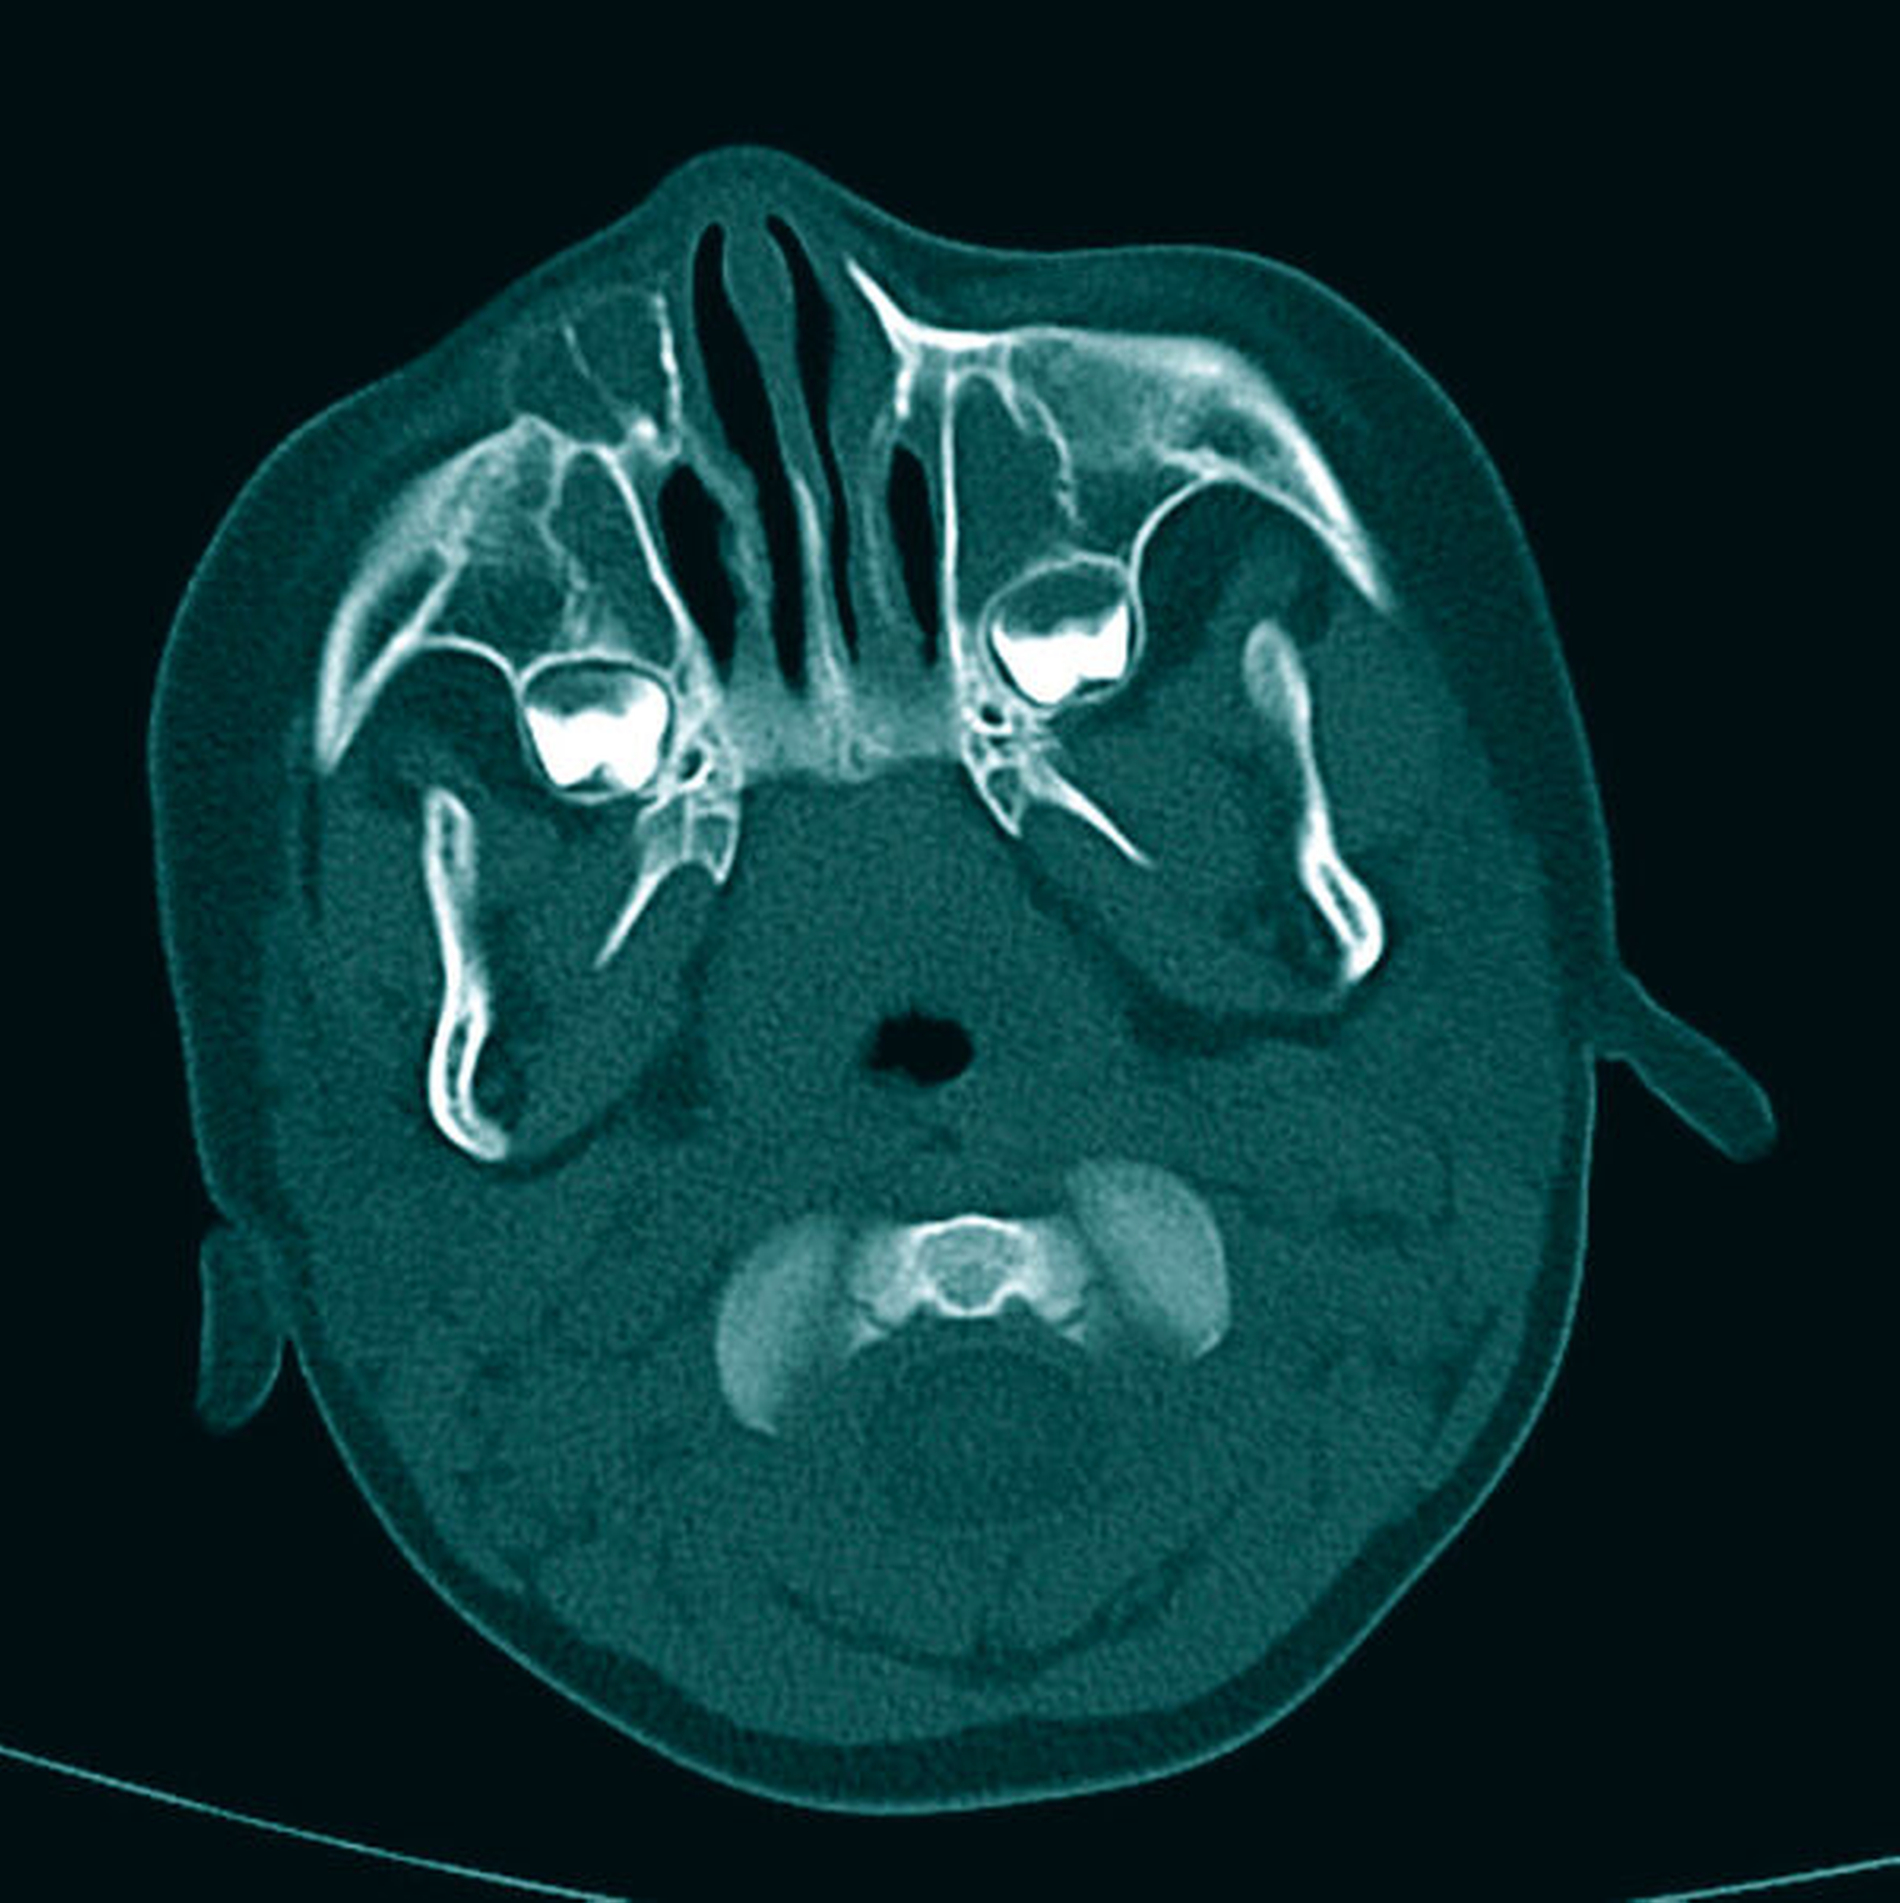

Eine Fraktur war nicht eindeutig ausschließbar. Aufgrund der detektierten Raumforderung wurde eine erweiterte Schnittbildgebung (Computertomografie) von radiologischer Seite angeraten. In der Computertomografie war eine rundliche Struktur paranasal/infraorbital ausgehend vom os maxillare erkennbar (Abbildungen 3 und 4).

Der Inhalt wies Dichtewerte von 33 HU auf, die damit denen einer proteinreichen Flüssigkeit entsprachen. Auf Höhe der Wurzel des oberen rechten Eckzahns war eine Kortikalisunterbrechung mit einem direkten Kontakt zur zystischen Raumforderung erkennbar. Dies zeigte sich ebenfalls über der Zahnanlage des bleibenden Eckzahns. Die Wandung der Raumforderung wies zarte Verkalkungen sowie eine zarte Septierung im kranialen Bereich auf.